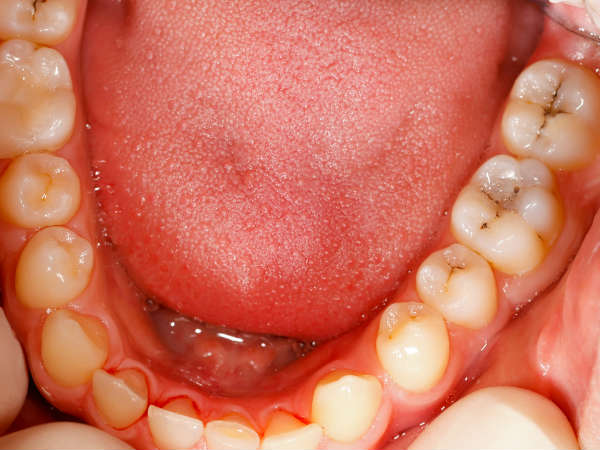

உங்க வாயில இந்த மாதிரி அறிகுறிகள் இருந்தா...அது வாய் புற்றுநோயோட அறிகுறியாம் தெரியுமா?

வாயில் மற்றும் உதடுகளில் புண்கள் பலருக்கு காணப்படுகின்றன. இது, முக்கியமாக வைட்டமின் சி குறைபாட்டால் ஏற்படுகின்றன. குணமடையாத புண்கள் இயற்கையில் புற்றுநோயாக இருக்கலாம் என்பதை கவனத்தில் கொள்ள வேண்டும்.

உதடு மற்றும் வாய்வழி குழி புற்றுநோய்களின் உலகளாவிய பாதிப்புகளில் ஒரு லட்சம் பேருக்கு 4 வழக்குகள் என மதிப்பிடப்பட்டுள்ளது. ஓரல் கேன்சர் என்று அழைக்கப்படும் வாய் புற்றுநோய், வாய்வழி குழியில் உருவாகிறது. இது உங்கள் வாயின் அனைத்து பகுதிகளையும் உள்ளடக்கியது. நீங்கள் வாயை அகலமாக திறந்து கண்ணாடியில் பார்த்தால் தெரியும். உதடுகளில் அல்லது வாயில் உள்ள செல்கள் மாறும்போது வாய் புற்றுநோய் உருவாகிறது. வாய் புற்றுநோய் மிகவும் பொதுவானது. ஆரம்ப நிலையிலேயே கண்டறிந்து சிகிச்சை அளித்தால் குணப்படுத்தலாம். ஒரு சுகாதார வழங்குநர் அல்லது பல் மருத்துவர் பெரும்பாலும் வாய்வழி புற்றுநோயை அதன் ஆரம்ப கட்டங்களில் கண்டுபிடிப்பார். ஏனெனில் வாய் மற்றும் உதடுகளை பரிசோதனை செய்வது எளிது. வாய்வழி புற்றுநோயின் மிகவும் பொதுவான வகை ஸ்குவாமஸ் செல் கார்சினோமா ஆகும்.

மற்ற எல்லா வகையான புற்றுநோயைப் போலவே, வாய்வழி புற்றுநோயின் ஆரம்ப அறிகுறிகளும் பெரும்பாலும் கவனிக்கப்படாமல் இருந்தால், உடலில் அதிகமாக வளரும். இருப்பினும், நோயின் பல்வேறு அறிகுறிகளை ஒருவர் கவனித்தால், புற்றுநோயின் வளர்ச்சியை ஆரம்ப நிலையிலேயே சரிபார்க்க முடியும் மற்றும் ஒரு நபர் நீண்ட காலம் வாழலாம். வாயில் புற்றுநோய் வளர்ச்சியைக் குறிக்கும் நுட்பமான அறிகுறிகளை பற்றி இக்கட்டுரையில் காணலாம்.

வாயின் உட்புறத்தில் வெள்ளை திட்டுகள்

வாயின் உட்புறத்தில் வெள்ளை திட்டுக்கள் அல்லது சில நேரங்களில் சிவப்பு நிற திட்டுகள் இருப்பது புற்றுநோயைக் குறிக்கலாம். இரைப்பை பிரச்சினைகள் அல்லது வாய் தொற்று போன்ற பல காரணங்கள் இதற்குப் பின்னால் இருந்தாலும், அது உங்கள் சுவை மற்றும் பேச்சை பாதித்தால், மருத்துவ உதவியை எடுத்துக்கொள்வது நல்லது.

வாய்க்குள் கட்டி

புற்றுநோய் கட்டிகளின் முதல் மற்றும் முக்கிய அறிகுறி ஒரு கட்டி வளர்ச்சி. வாயின் மேற்பரப்பில் ஒரு கட்டி வளர்ச்சி இருந்தால் அது நிச்சயமாக கவனிக்கப்பட வேண்டும். இதுபோன்ற சந்தர்ப்பங்களில், கட்டி தானாகவே போகும் வரை காத்திருக்க வேண்டாம். அதற்கு பதிலாக, மருத்துவரிடம் சென்று பரிசோதனை செய்யுங்கள்.